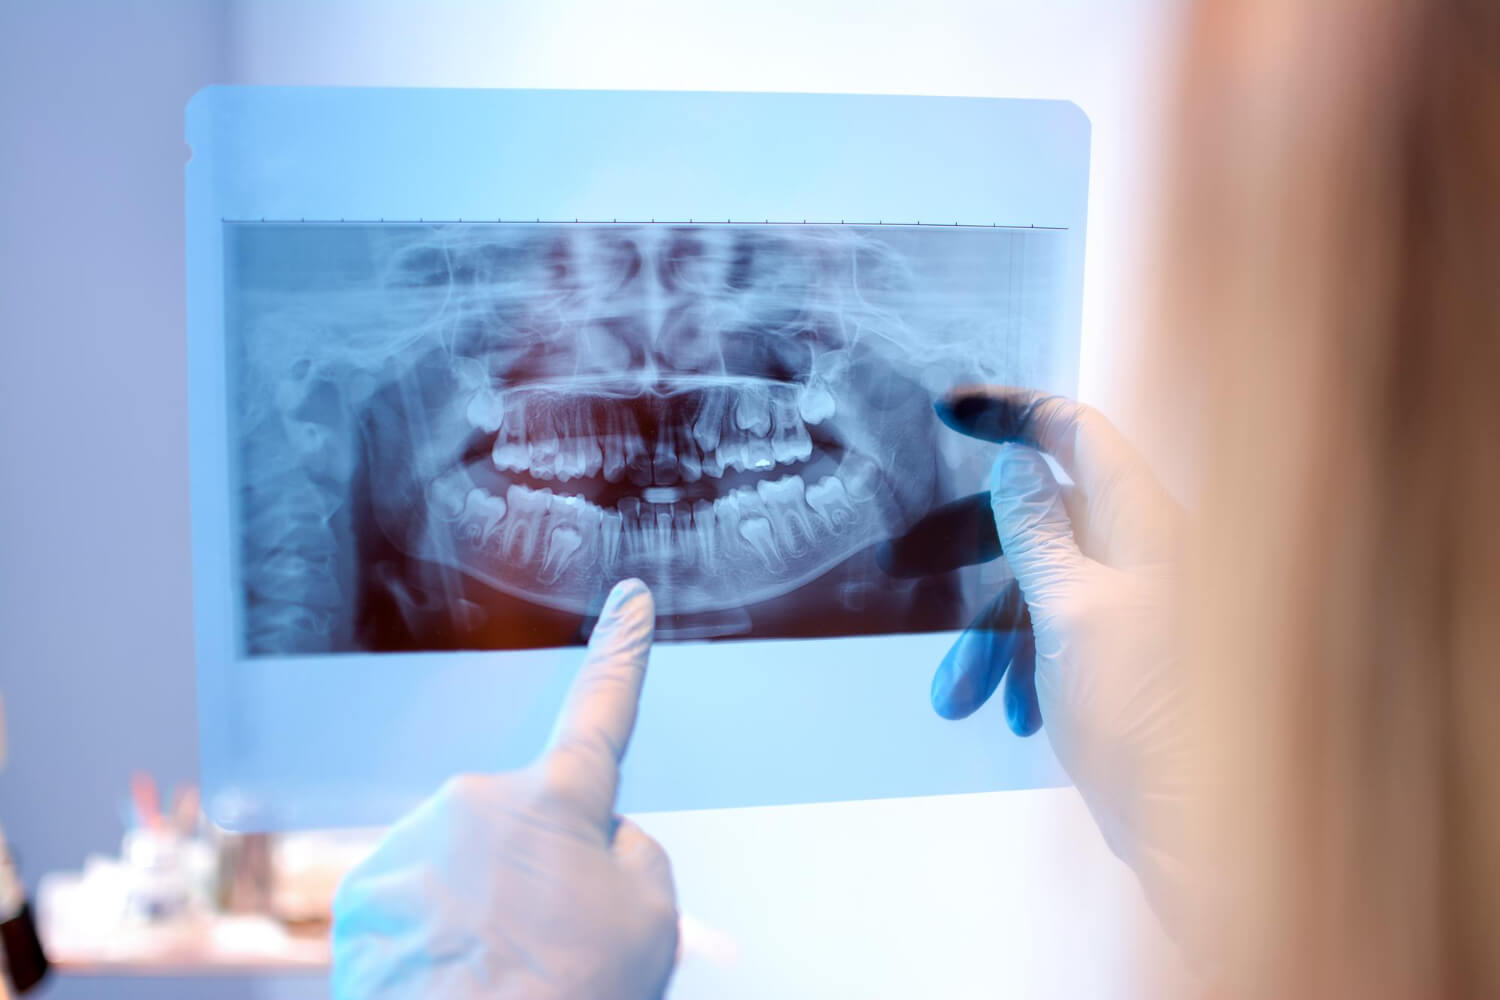

Equipos de última generación para diagnósticos precisos y tratamientos más cómodos y rápidos.